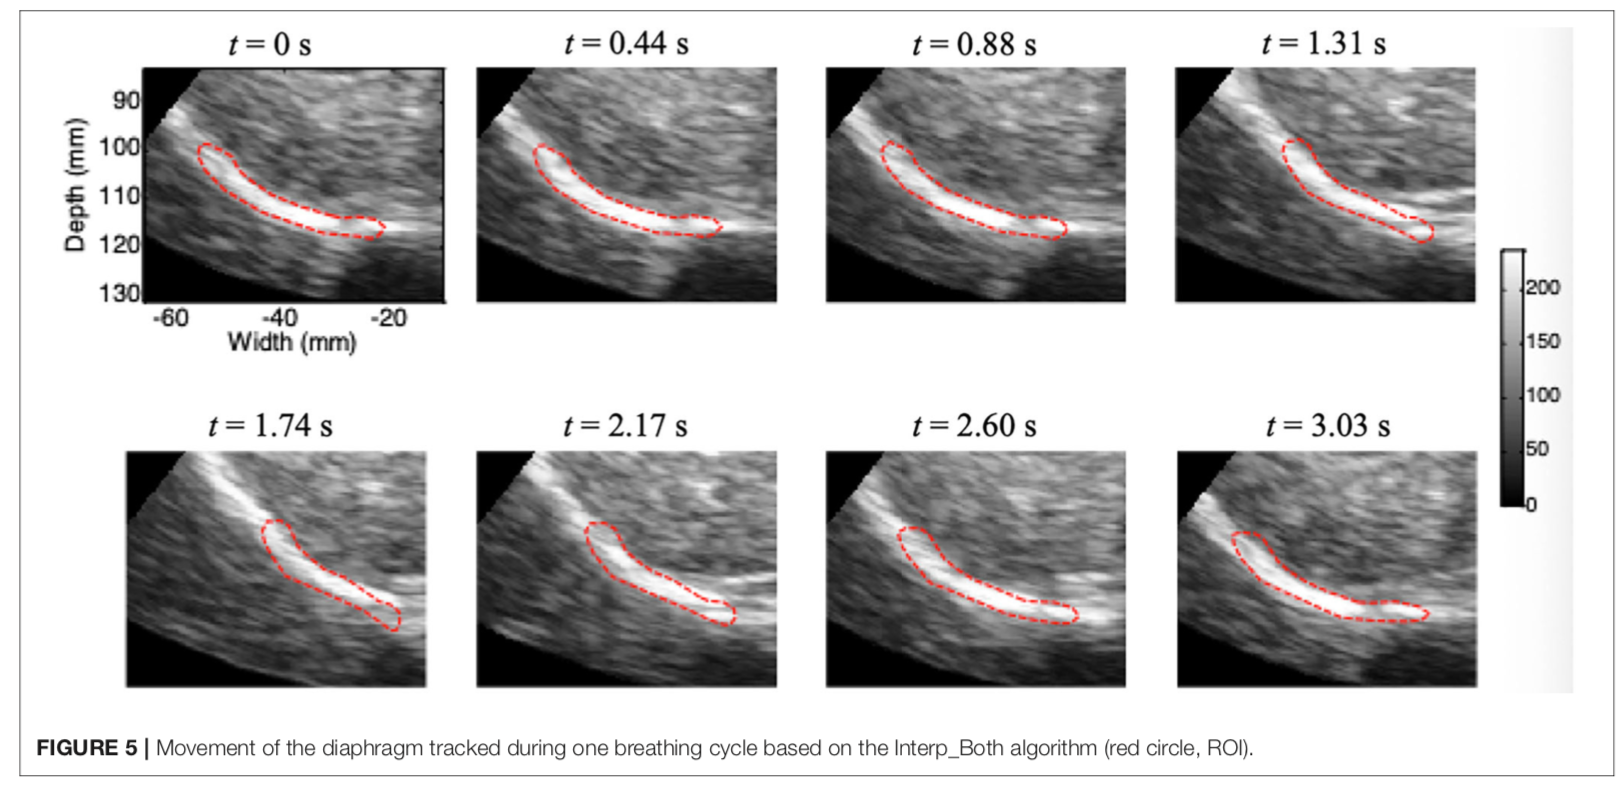

叶熊博士潜心于教学和自然科学研究,不忘初心、默默耕耘。分别主持厅局级和省部级项目各1项,校级项目3项,总资助经费30万元,发表第一作者SCI论文3篇,累计影响因子11.133分。于2017年10月,在《Int J Chron Obstruct Pulmon Dis》杂志(IF:3.355)发表题为“Echo intensity of the rectus femoris in stable COPD patients”的研究论文1篇,该研究探索了一种超声图像回声强度定量方法,用于评估慢性阻塞性肺病患者股四头肌功能,有助于早期诊断慢性阻塞性肺病患者的骨骼肌功能失调;于2021年5月,在《Frontiers in Medicine》杂志(IF:5.091)发表题为“A Novel Normalized Cross-Correlation Speckle-Tracking Ultrasound Algorithm for the Evaluation of Diaphragm Deformation”的研究论文1篇,该研究首次把互相关归一算法用于膈肌超声斑点追踪,为研究膈肌动力学提供了一种创新性的方法。该成果是叶熊老师和清华老员工物工程系罗建文研究员团队合作的阶段性成果